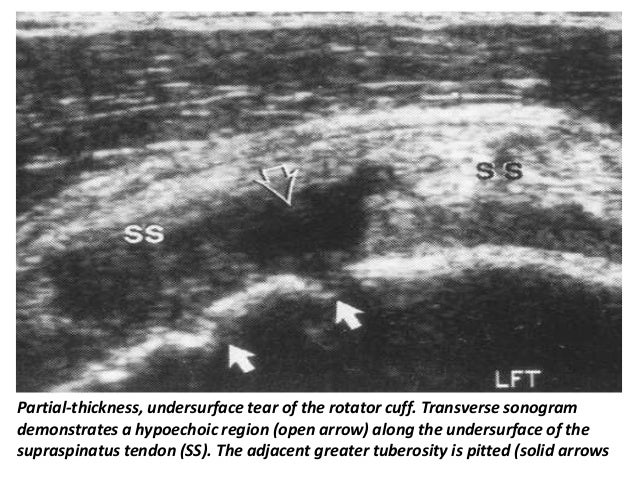

22. 22. Sonographic detection, localization, and characterization of partial-thickness cuff tears have been described only recently. Proposed criteria include a hypoechoic defect that involves the articular or bursal surface, a focal hypoechoic zone within the substance of the cuff, a large linear echogenic focus within the cuff substance, thinning of the cuff (marked during passive movement), and a straight outer cuff border (loss of convexity). Criteria that address intrasubstance findings may produce a relatively high false-positive rate because these “defects” may not be visualized by means of correlative methods such as arthrography, arthroscopy, and surgery. Van Holsbeeck et al achieved 93% sensitivity and 94% specificity with two criteria: a mixed hyper- and hypoechoic region or a hypoechoic discontinuity that involves either the bursal or articular surface. The former is attributed to penetration of torn cuff fibers by joint fluid. An associated finding described by these investigators is that of “pitting” of the greater tuberosity

31. 31. Partial-thickness, undersurface tear of the rotator cuff. Transverse sonogram demonstrates a hypoechoic region (open arrow) along the undersurface of the supraspinatus tendon (SS). The adjacent greater tuberosity is pitted (solid arrows